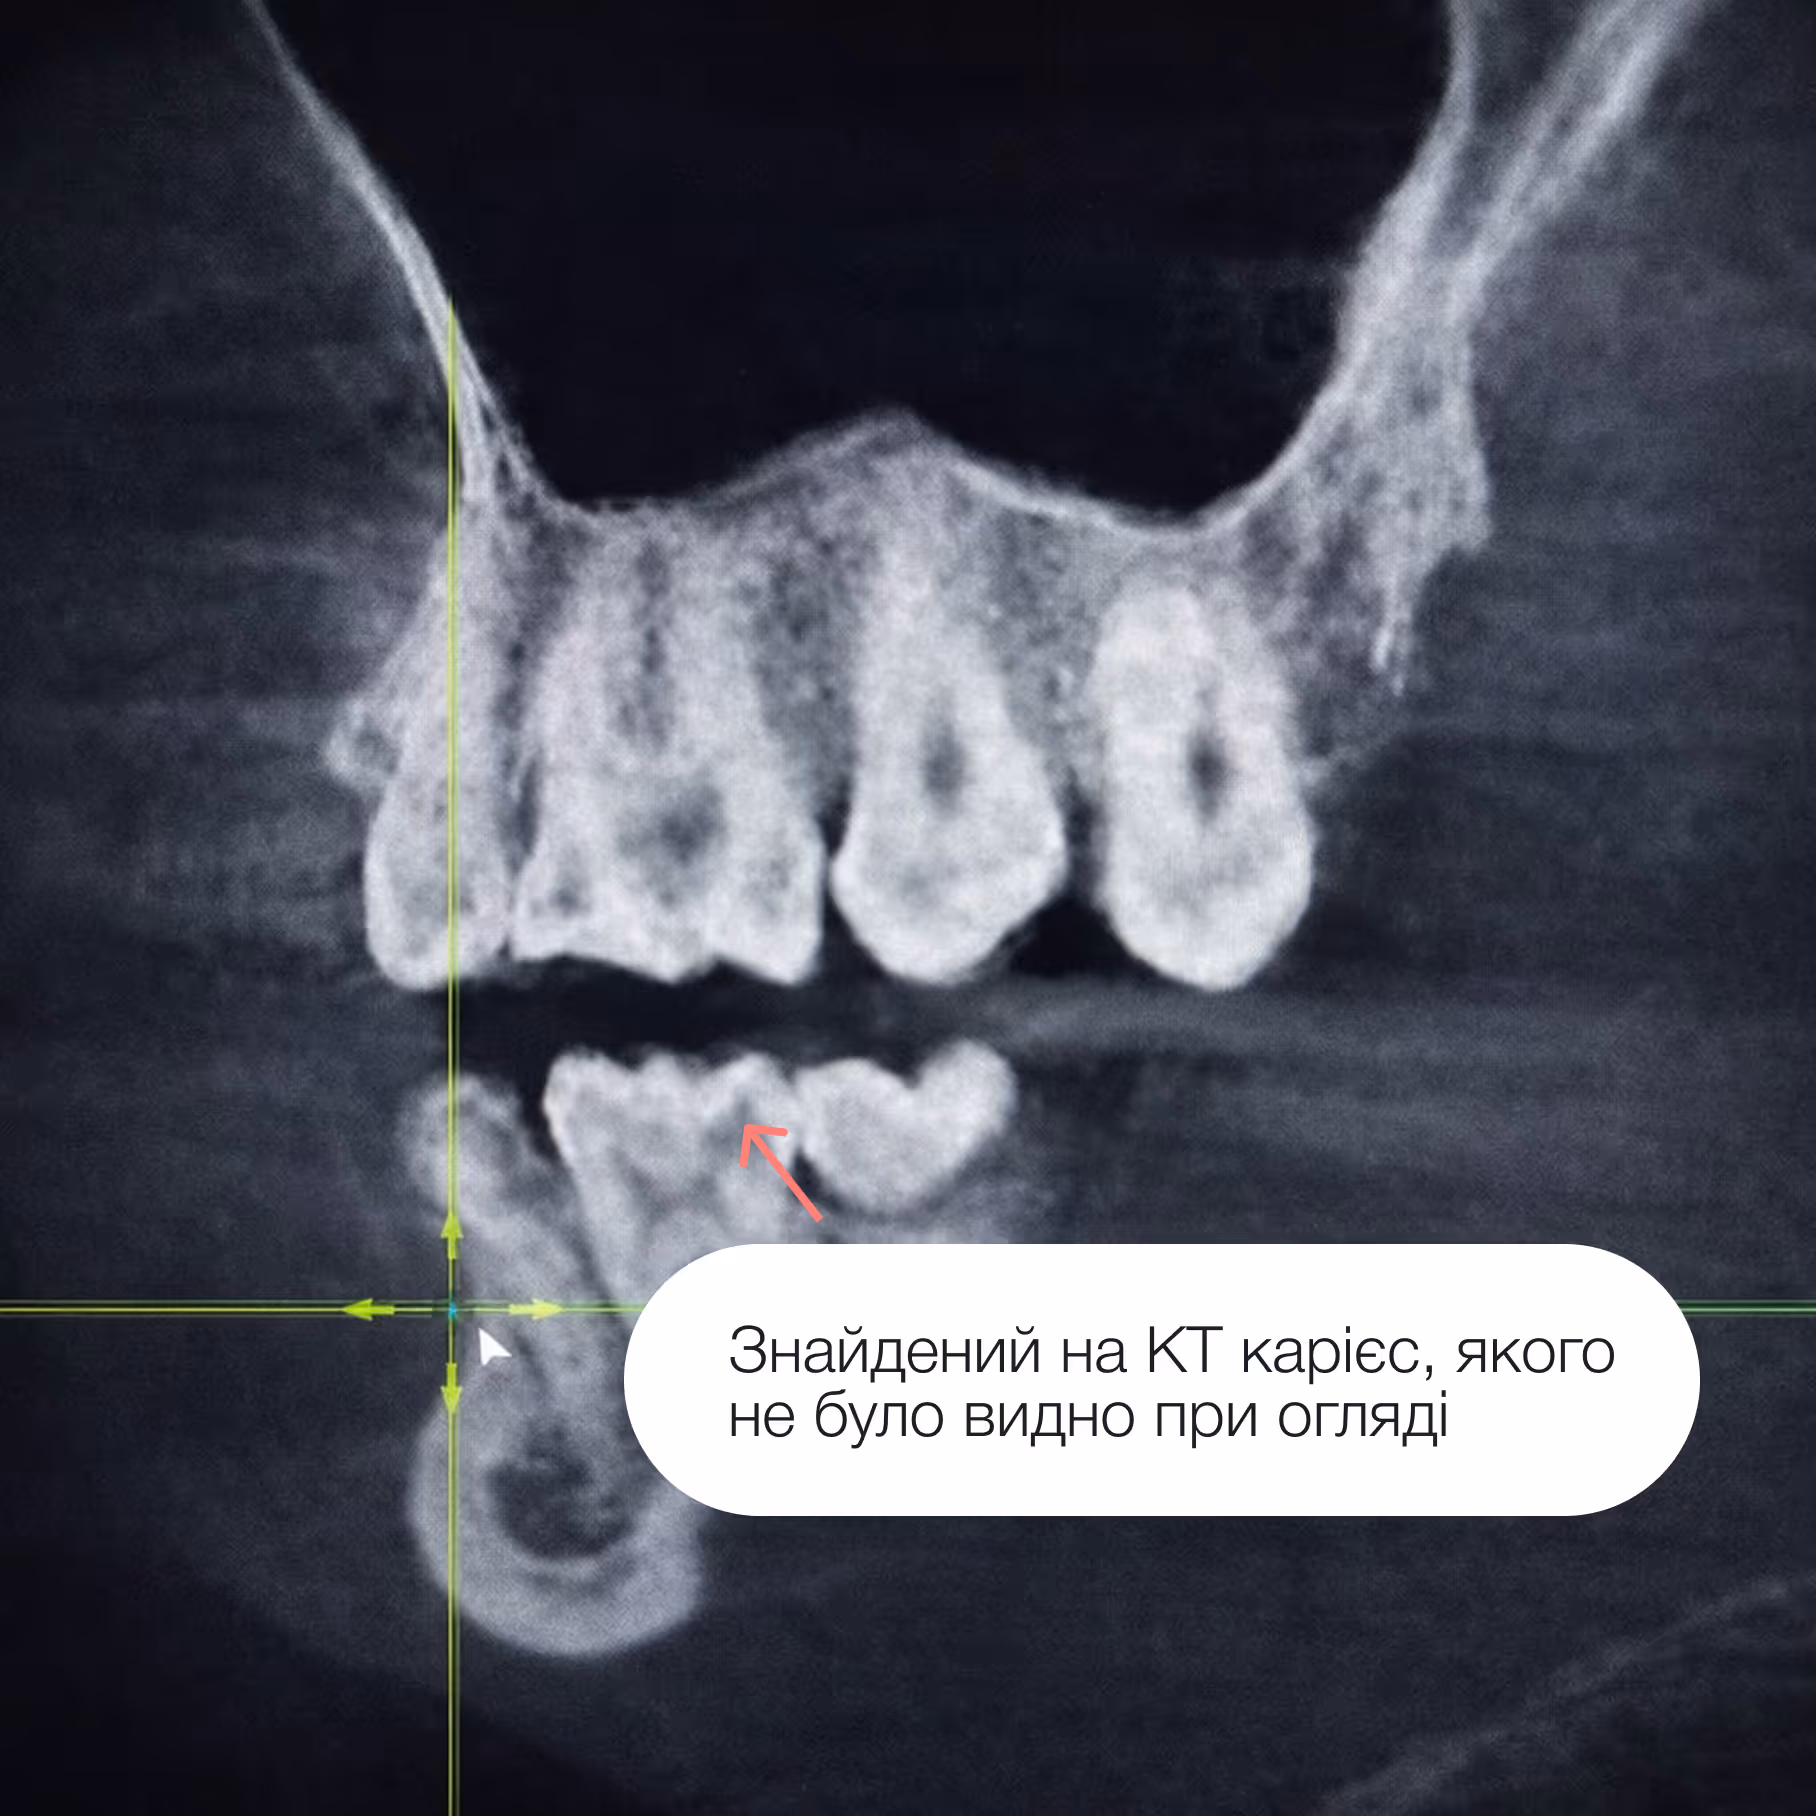

Карієс поширюється зсередини, і якщо почекати, ураження стане глибшим. Це може призвести до:

– лікування каналів,

– керамічних вкладок,

– коронок,

– значно дорожчого лікування.

Раннє втручання дозволяє повністю зберегти зуб і уникнути ускладнень.